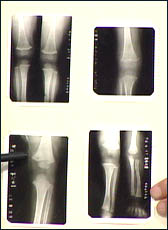

主持人:有的孩子在12-13岁时长得很快,但到了13-14岁时长高速度就明显减慢,这是什么原因? 关立夫:小儿身高的生长主要依靠的是骨骼的生长,骨骼有两部分的生长影响身高1、脊柱、颈椎、胸椎、腰椎。2、长骨、股骨、胫骨、主骨。小孩的骨头分两部分即骨干和骨骺,骨干和骨骺之间有一个缝叫软骨,软骨可以不断增殖和钙化。来看一张下肢的X光片,长的是骨干,小的是骨骺,不断的生长是有规律的,到了青春期以后(18岁以后)软骨部分就会变得越来越窄,从一张手的X光片中可以看到当骨骺和骨干愈合后就不会再生长了,身高也就停止了。

主持人:北京杨女士 50岁 我女儿13岁时身高1米5,但在检查中她的骨龄已有18岁了。今年15岁,身高1米52,请问为什么会有18岁的骨龄,她还有长高的可能吗? 关立夫:孩子的身高增长机会不会很大了,因为骨龄到了18岁骨骺和骨干就基本愈合了,只会有轻微的增大,长长就比较困难了。

主持人:山西陈女士 42岁 用什么样的方法能够预测孩子的身高? 关立夫:可以到门诊照一张骨龄的片子(手部),身高与骨龄等其他因素相结合就可以预测出孩子的身高。